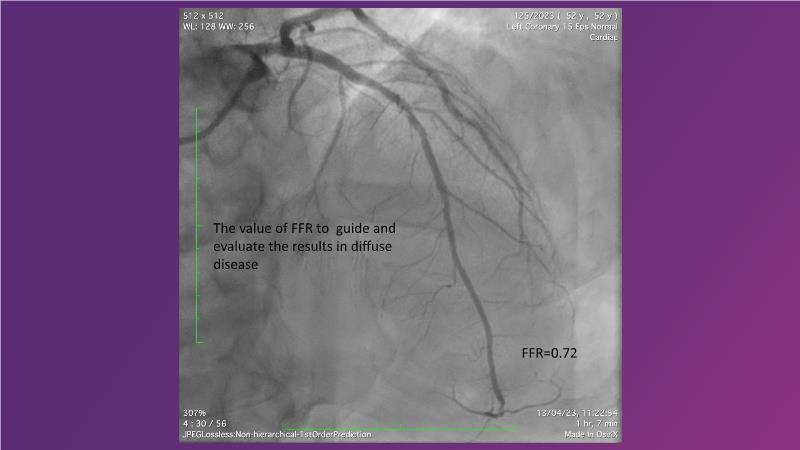

Follow this session to discover how accurate resting index can inform decision-making for DCB in CTO patients and understand the role of physiology in a new PCI workflow for complex MVD. Thus, you will learn about a DCB intention-to-treat strategy guided by post-PCI coronary physiology in complex lesions, review new procedural techniques and workflows from real-world cases, and explore the pros and cons of this novel approach.

- To learn about DCB intention-to-treat strategy guided by post-PCI coronary physiology in complex lesions

- To review new procedural technique and workflow from real world patient cases